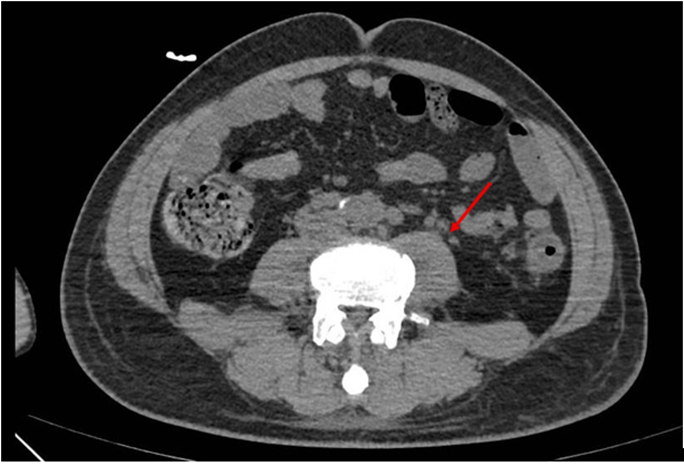

Abdominal CT scan (Figure 1): Irregular thickening of the descending colon wall with blurred surrounding mesenteric fat, and multiple enlarged lymph nodes in the iliac vessels, pelvic cavity, and retroperitoneum.

Figure 1: Abdominal CT scan